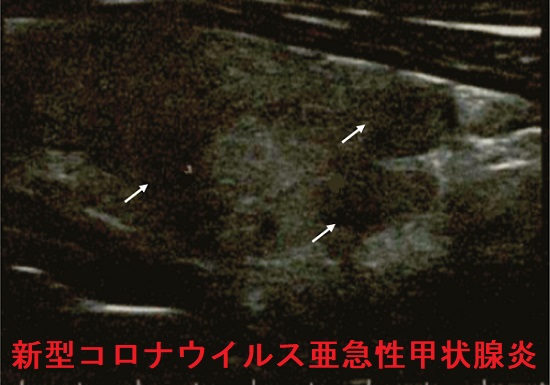

イタリアの新型コロナウイルス亜急性甲状腺炎 超音波(エコー)画像

矢印は炎症部

(J Clin Endocrinol Metab. 2020 Jul 1;105(7):dgaa276.)